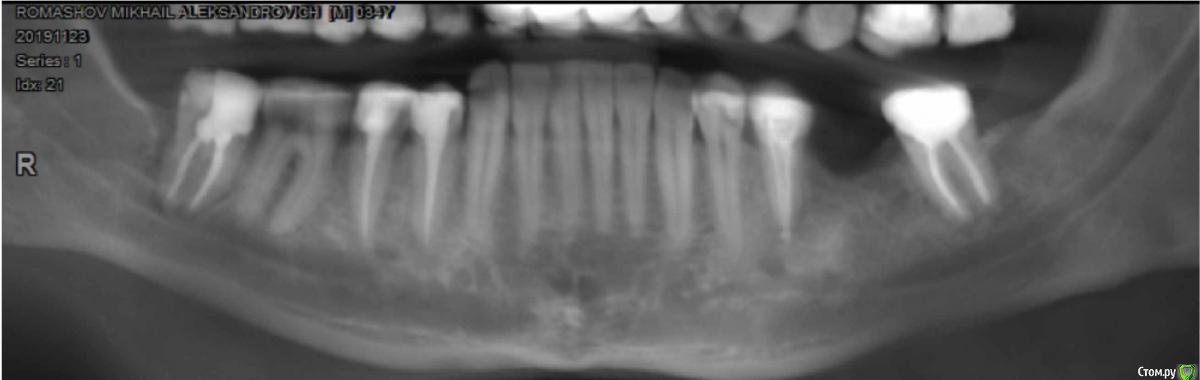

Trigger Опубликовано 28 января, 2020 Автор Поделиться Опубликовано 28 января, 2020 (изменено) Верх покрыл коронками, нижние (37, 35, 44, 45, 47) по плану. За все время лечения врач говорил только об импланте. Сразу не ставили, тк было воспаление у 35.Сделал свежее КТ. Все обговорили, что большая впалость десны, потребуется костная и десневая пластика и установка импланта. Мне оставалось только выбрать системы с которой врачи работают Astra tech или Dentium. Почитал, особой разницы не увидел. Везде вывод один, зависит от качества установки, а не фирмы. Переплачивать 10к смысла не вижу. Саму операцию врач передал коллеге. Он посмотрел, сказал, что идеально сделать не сможет и между импланом и зубами 35 и 37 останутся треугольные пустоты. Срок жизни 35, 37 после покрытия коронками оставляет 5-15 лет (тут у меня большие вопросы. Что у 35 было воспаление, может повториться и сколько ему останется это понимаю. но 37 пломбе более 10 лет меня не беспокоит) придется на этом участке ставить три импланта подряд.Предложил сейчас с костью, десной ничего не делать. Поставить мост 35-37. Когда с зубами что то случится сделать 2 импланта 35, 37 и тот же мост.Когда мне это все озвучили было очень неожиданно, тк вариант с мостом ранее не рассматривался вообще. Взял паузу на подумать.Пока склоняюсь к варианту ставить имплант. Мост даст бОльшую нагрузку на 35 и 37. Изменено 28 января, 2020 пользователем Trigger Ссылка на комментарий

Bier Опубликовано 29 января, 2020 Поделиться Опубликовано 29 января, 2020 Без КТ сложно судить, но мне кажется, что возможно установить имплантат только с десневой пластикой. Без пластики костной ткани. Ссылка на комментарий